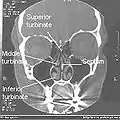

Normal Nose CT Front cross section